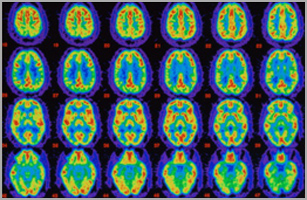

Effectuez notre Visite du cerveau interactive

Voir de quelle façon la maladie d'Alzheimer affecte la santé du cerveau.